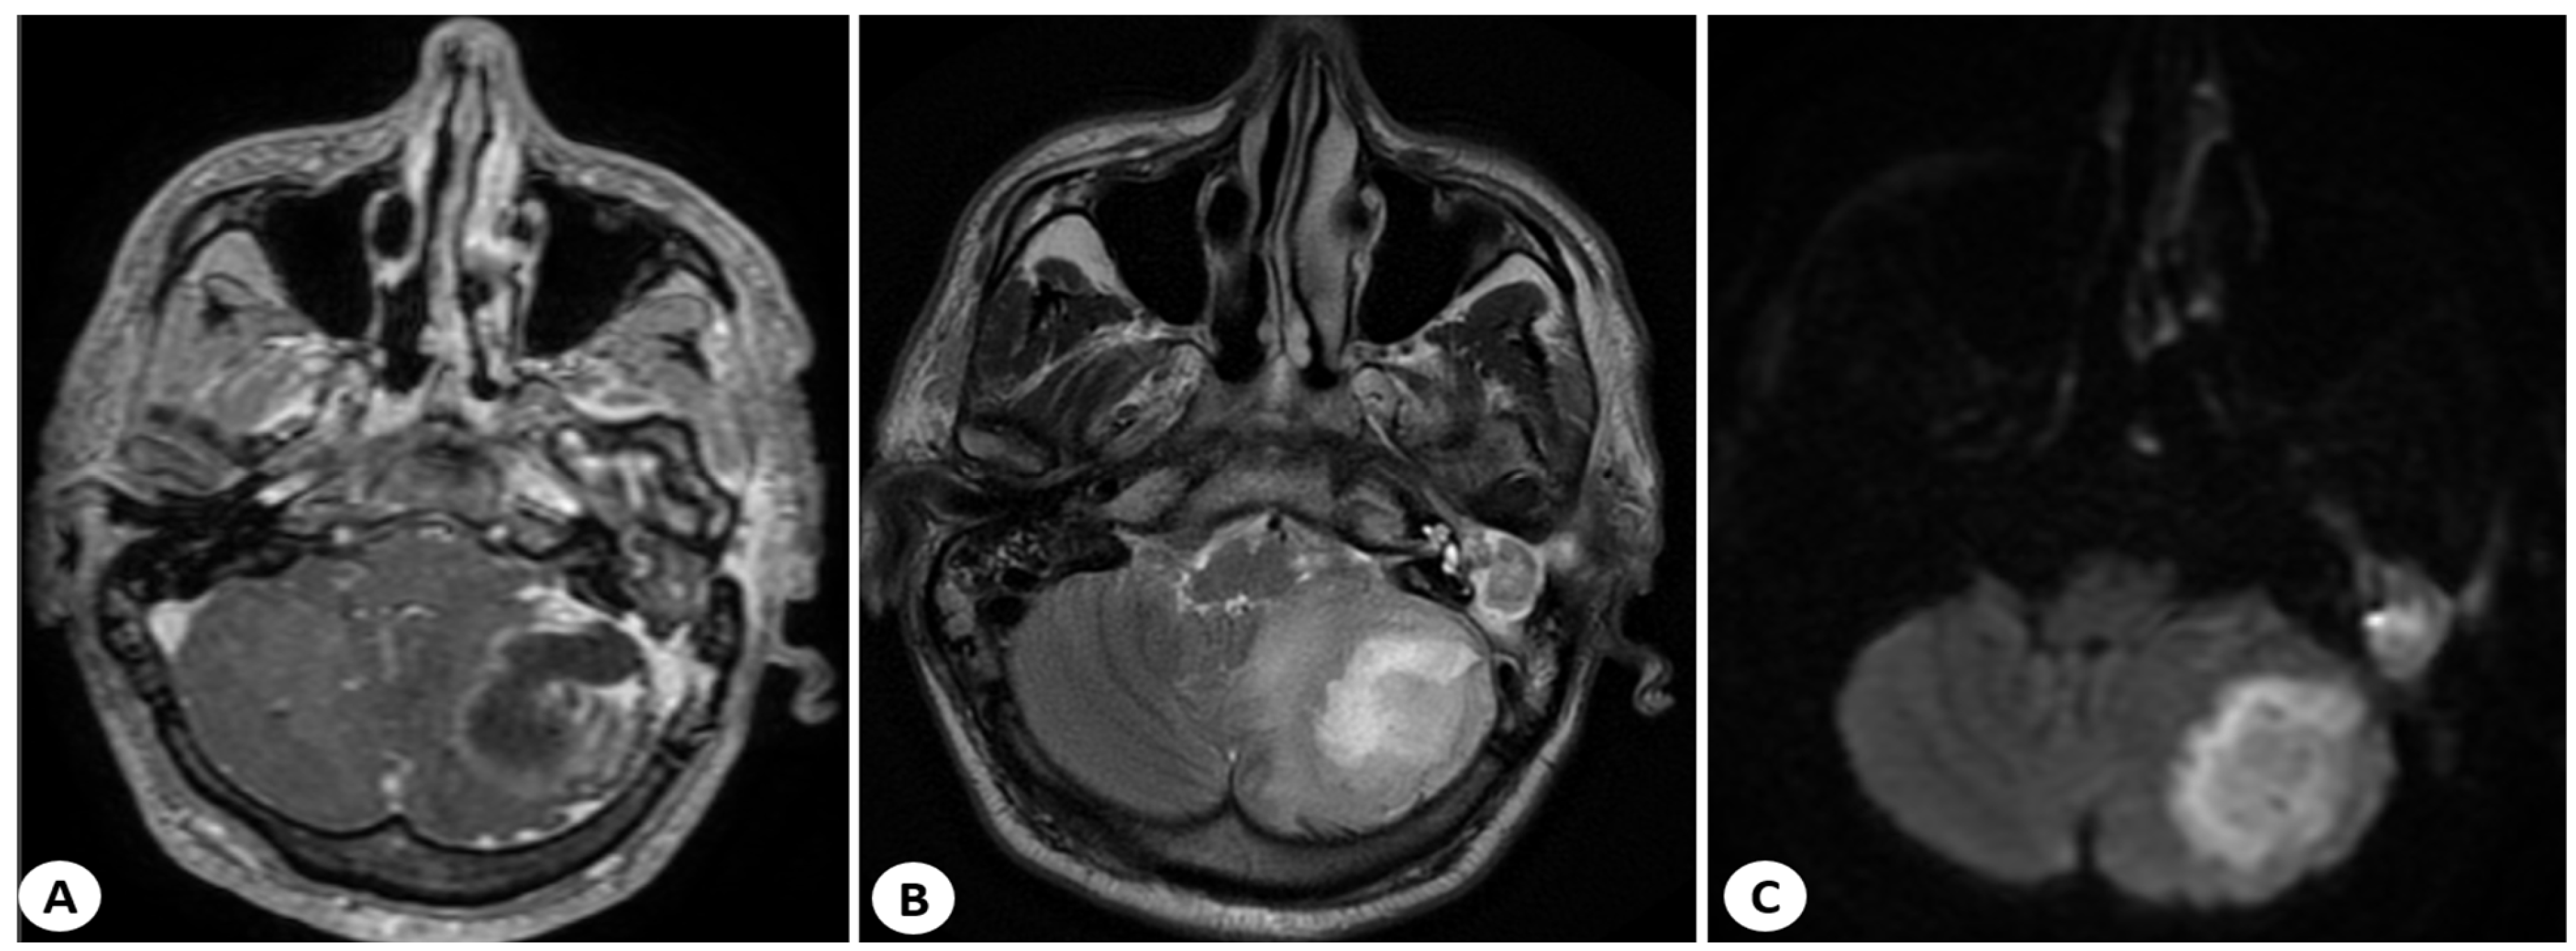

2.2.2. Imaging Studies

3.5. Imaging Studies